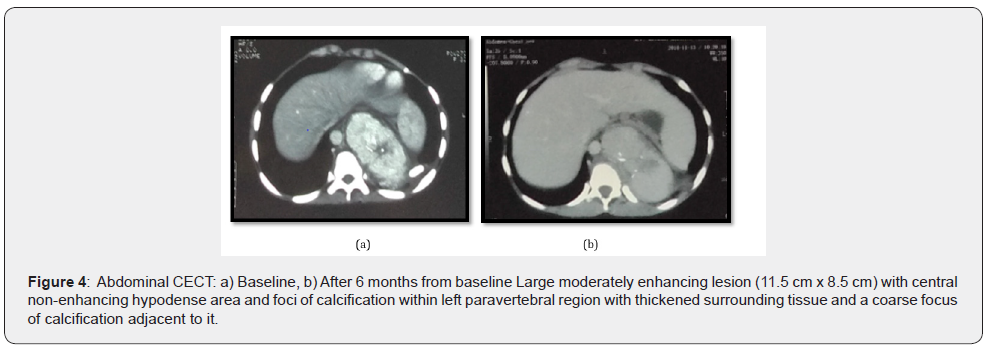

Hematology and biochemistry reports were normal. Biopsy for histopathological examination from the lower lip was consistent with oral LP (Figure 3). For abdominal pain, ultrasonography of the abdomen and pelvis was done which showed, a welldefined heterogenous hypoechoic mass lesion with few foci of calcification within and with minimal internal vascularity abutting the hilar surface spleen and upper pole of left kidney. For further evaluation CECT (contrast-enhanced computed tomography) abdomen and pelvis was done, which revealed large moderately enhancing lesion of size 11.5 cm x 8.5 cm with central non-enhancing hypodense area (likely necrotic area) and foci of calcification within in left paravertebral region (extending from upper border of L1 up to upper border of T8 vertebral body) with thickened surrounding tissue and a coarse focus of calcification adjacent to it and sclerosis of T9, T10, T11 vertebral bodies(more on left), likely to be neuroblastic tumor (Figure 4) and suggested for cytohistopathological correlation. Trucut biopsy of the left suprarenal retroperitoneal mass showed features of low-grade spindle cell tumor of fibrohistiocytic origin (Figure 5) and immunohistochemistry showed tumor cells positive for viamentin and SMA (Smooth muscle actin) (Figure 6) and the features were suggestive of inflammatory myofibroblastic tumor.